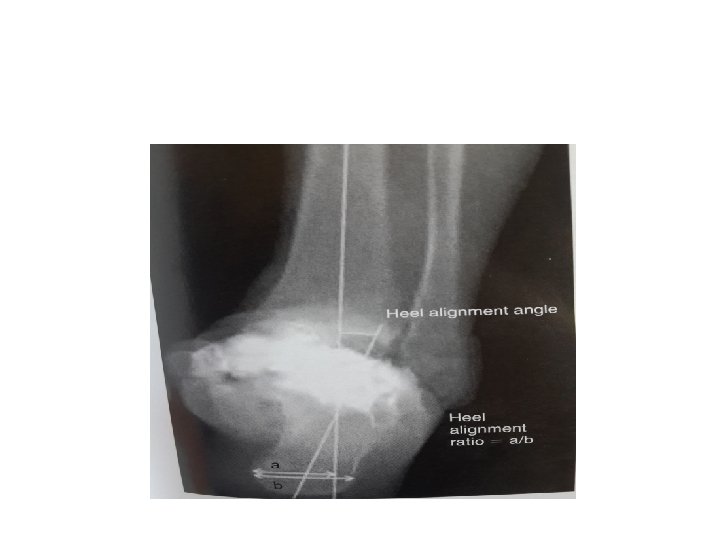

TECHNIQUES • NEUTRAL FLEXION/EXTENSION, EXTERNAL ROTATION OF 5 DEGREES , 5 DEGREES OF VALGUS AND SLIGHT POSTERIOR TRANSLATION OF THE TALUS UNDER THE TIBIA • FUSION OF ANKLE JOINT IN PLANTAR FLEXION RESULTS IN GENU RECURVATUM